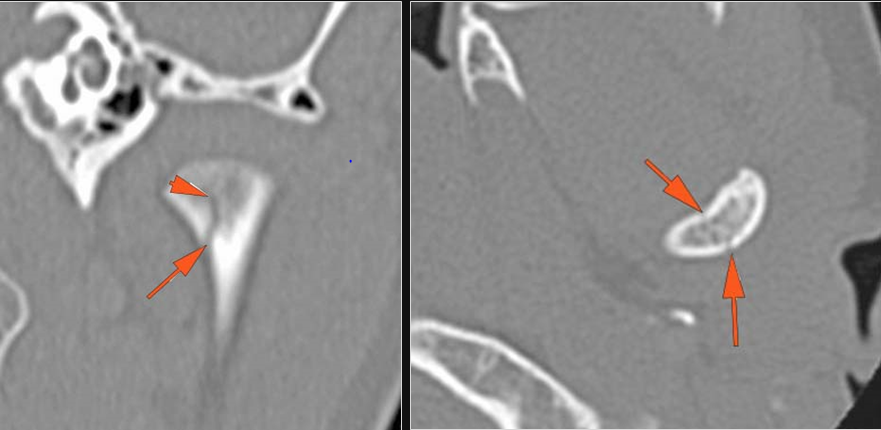

The condylar head and fossa as well as the temporomandibular joint space are fractured and/or dislocated. [Yes/No]

There is condylar fracture either within or outside of the joint capsule, or with or without involvement of the articular surface of the condylar head. [Yes/No]

There is evidence of radiodense intra-articular osteochondral fragments. [Yes/No]

There is bony injury or displacement of the external auditory canal and/or other evidence of temporal bone injury. [Yes/No]